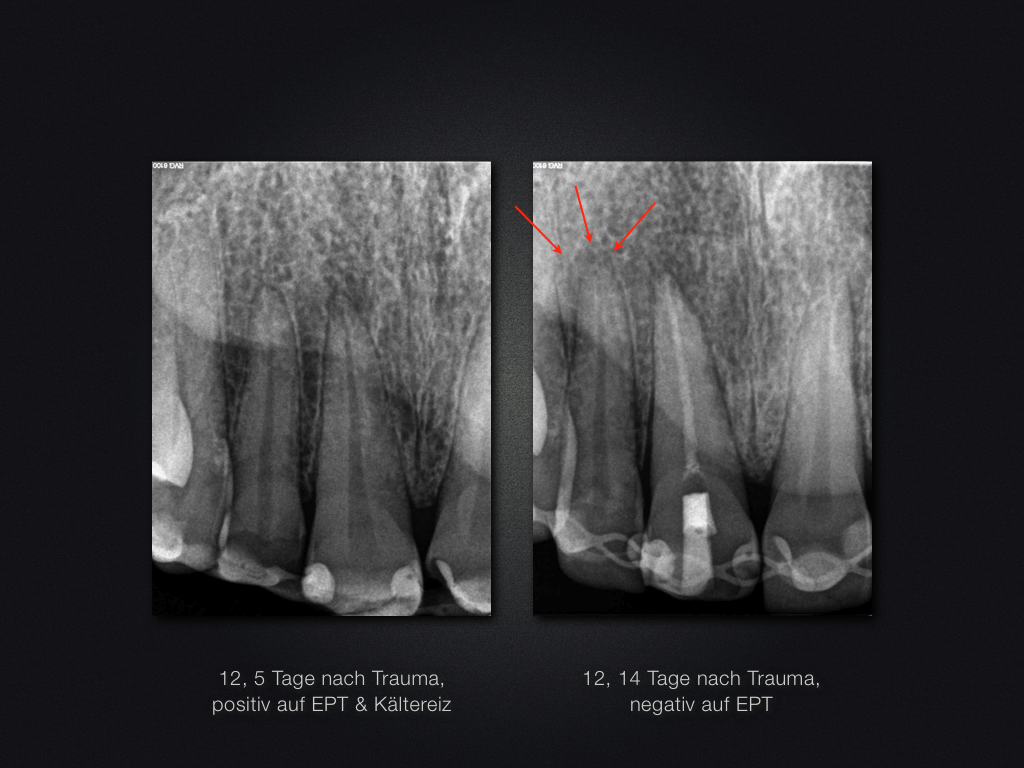

Trauma-„Zweitversorgung“